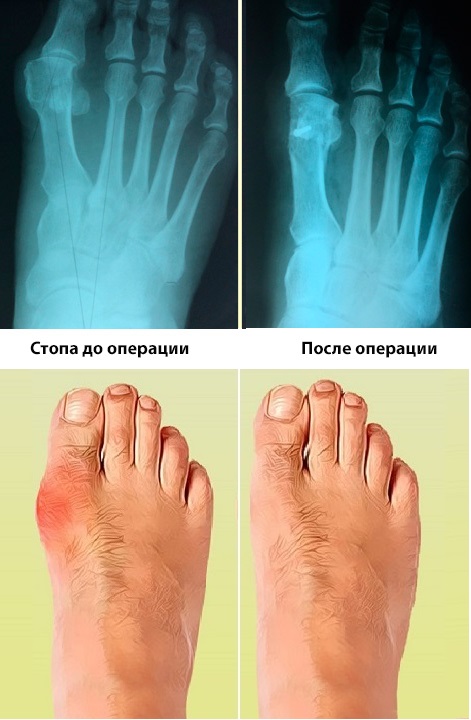

Среди всех видов ортопедической патологии одно из первых мест занимает вальгусная деформация стопы (если быть точнее, первого пальца). Казалось бы, такая распространенная проблема должна вовремя диагностироваться, ведь для ее лечения существуют безоперационные методики: применение шин, корректоров, бандажей, стелек. Но на практике многие пациенты не знают, как лечить вальгусную деформацию стопы и боятся, что им потребуется оперативное лечение. Поэтому они откладывают посещение специалиста до тех пор, когда деформация становится значительной и начинает доставлять дискомфорт. Описание Hallux valgus (как еще называют вальгусную деформацию первого пальца стопы) – это патологический разворот первой пястной кости внутри, который приводит к искривлению первого пальца наружу. Эта патология встречается наиболее часто у женщин среднего/пожилого возраста, сопровождается болевыми ощущениями и приводит к затруднениям при ходьбе, проблемам при выборе обуви. Причины появления Своим появлением вальгусная деформация стопы обязана наличию обуви: у представителей племенных поселений такая патология не встречается, так как хождение босиком поддерживает в постоянном тонусе мышцы и сухожилия ног. В развитых странах наиболее значимыми причинами возникновения такой деформации считают ношение неправильной обуви и плоскостопие. К более редким факторам относят:

Ослабленные мягкие ткани перестают удерживать свод, и кости «разъезжаются». Первая плюсневая кость разворачивается, а прилежащий к ней плюсне-фаланговый сустав становится нестабильным, что приводит к искривлению первого пальца. Постоянное травмирование обувью внутренней части расширенной стопы приводит к разрастанию костной ткани (образованию «шишки»), огрубению кожи (появляются мозоли, натоптыши), хроническому воспалению сустава/околосуставной сумки. В процесс вовлекаются другие части стопы. Симптомы вальгусной деформации Когда угол между костями плюсны не превышает 5-20º и палец отклоняется не больше, чем на 40º (т.е. наблюдается I степень вальгусной деформации), симптомы незначительны: болезненные ощущения появляются к вечеру, а за ночь, особенно при использовании ночного бандажа, полностью проходит. Травмирующаяся из-за трения кожа краснеет, появляются мозоли. Hallux valgus выражен незначительно. При увеличении угла между костями плюсны до 20-30º и отклонении пальца до 40-70º (т.е. при II степени вальгусной деформации) боль становится постоянной, растет «шишка», кожа у основания первого пальца грубеет, на подошве появляются натоптыши (из-за неправильной нагрузки на отделы стопы). Воспаление околосуставной сумки становится хроническим. На этой стадии все еще эффективно консервативное безоперационное лечение, в том числе применение вальгусной шины. Когда угол между костями плюсны превышает 30º и первый палец отклонен более чем на 70º (т.е. имеется III степень hallux valgus), боль не исчезает, т.к. она обусловлена не только хроническим воспалением и атипичной нагрузкой, но еще и сдавливанием нервов смещенными костями. На этом этапе применение ортопедических конструкций приносит временное облегчение. Плюсне-фаланговый сустав практически неподвижен, в его проекции кожа грубая, могут образовываться язвы. Для восстановления функций стопы требуется хирургическое вмешательство. Диагностика болезни После выявления патологического отклонения пальца врач (как правило, ортопед или травматолог) назначают следующие обследования:

Операция при вальгусной деформации При такой патологии как вальгусная деформация стопы лечение оперативным путем возможно несколькими путями. На ранних стадиях ее можно исправить миниинвазивными хирургическими вмешательствами (рассекание и сшивание сухожилий), которые направлены на восстановление мышечной тяги. Параллельно возможно удаление костного экзостоза («шишки»). При более тяжелых стадиях применяют операции, при которых проводят клиновидную остеотомию, а затем скрепляют их металлическими конструкциями («шурупами» или «спицами») для восстановления оси. В особо сложных проводят остеотомию клиновидных костей стопы, операция проводится одновременно на обеих стопах. В послеоперационном периоде пациенты ходят уже на второй день в специальной обуви «Барука». Сроки реабилитации зависят от степени вальгусной деформации, возраста пациента и сроков сращения плюсневых костей в послеоперационном периоде. В среднем около 1,5 до 2,5 месяцев. ТЕЛЕФОН ОТДЕЛЕНИЯ ТРАВМАТОЛОГИИ И ОРТОПЕДИИ: +7 727 261 04 34